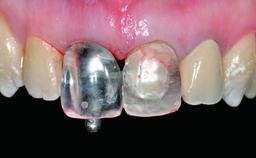

Replacement of a Missing Upper Left Central Incisor: Late Placement of an RC Bone Level Implant, CAD/CAM Zirconia Abutment

| Abutment Type | CAD/CAM |

| Prosthesis Type | FDP |